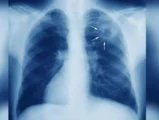

Τα «νέα» αυτά δεν είναι καλά για την καρδιά, καθώς όπως αναφέρει δημοσίευμα στην ιστοσελίδα time.com, προηγούμενες έρευνες σε ζώα έχουν δείξει ότι ο μεταβολίτης αυτός βοηθά στη μεταφορά της χοληστερόλης στις αρτηρίες, όπου σχηματίζει επικίνδυνες πλάκες, που μπορεί να οδηγήσουν σε καρδιακές παθήσεις.